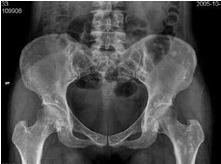

脆弱性骨硬化又称骨斑点症,播散型凝集性骨病及点状骨全身多数骨骼上出现广泛散播的细密斑点,一般不产生临床症状,大多数因其他原因作X线检查时偶然发现。本病最好发于管状骨的骨骺、干骺端等松质骨内,还可见于某些扁骨和不规则骨内 。据病理观察骨松质内有多个灰白色圆形或椭圆形致密小骨块。